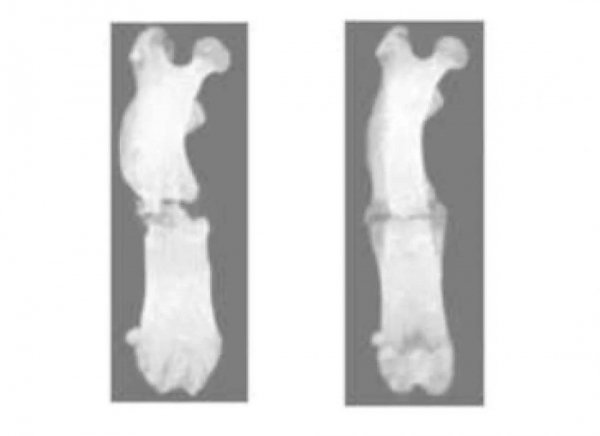

연구자들은 두 가지 방법으로 쥐의 다리를 부러뜨렸다. 24마리의 쥐로 구성된 한 그룹은 일반적으로 치료가 쉬운 정상적인 골절을 보였다. 20마리의 다른 그룹 쥐는 치유가 일반적으로 연장되거나 일어나지 않는 비유합 골절이었다.

치료실험을 위해 일부 쥐에는 비열 대기압 플라즈마를 조사했다. 이는 정상 골절 그룹에 큰 이점을 제공하지 않았으나 비유합 골절이 있는 쥐의 치유 및 회복 시간을 향상시켰다. 조사된 비유합 쥐의 치유된 부위의 강도 역시 조사하지 않은 쥐에 비해 약 3.5배 더 강했다.